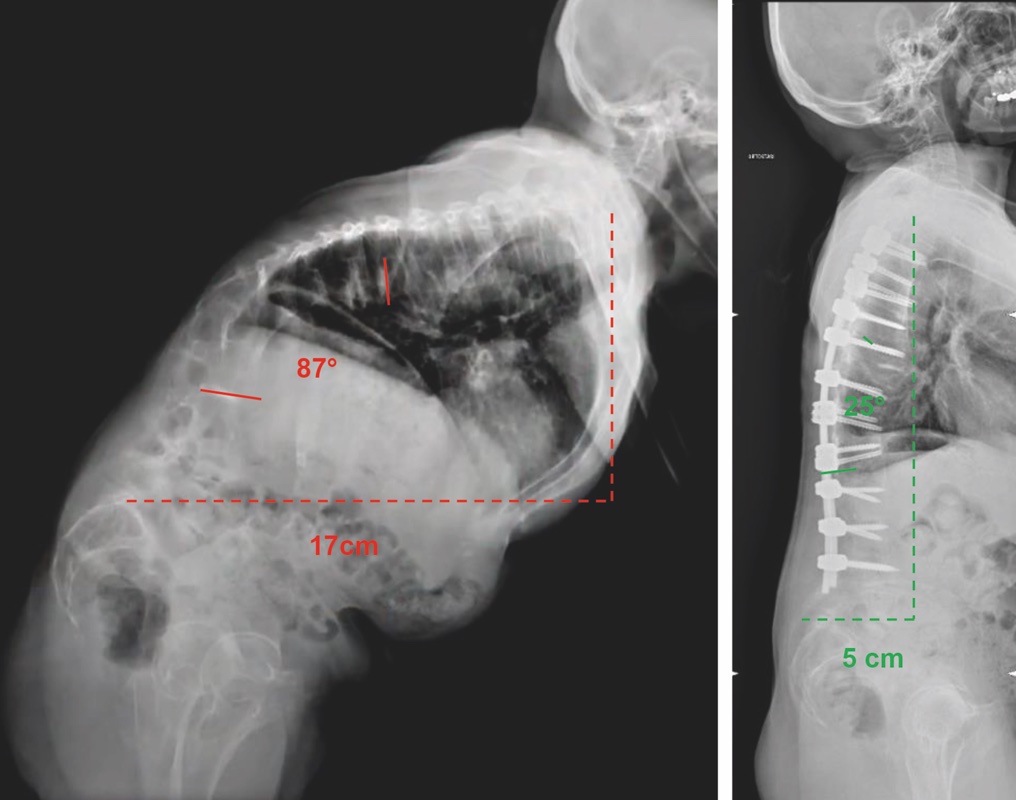

In caso in cui il paziente fosse candidabile alla chirurgia, è imprescindibile un’attenta tipizzazione delle caratteristiche della singola deformità, in termini di raggio di curvatura e di rigidità, col fine di individuare la strategia correttiva più appropriata. In particolare, deformità ad ampio raggio e/o flessibili, possono essere dominate tramite osteotomie della colonna posteriore (di tipo Ponte e Smith-Petersen), eventualmente multiple, cercando di dissipare la correzione su ogni singolo livello. In caso di deformità a breve raggio e/o rigide, risultano necessarie aggressive osteotomie tricolonnari, come la PSO (osteotomia di sottrazione peduncolare) e la VCR (vertebrectomia). Le osteotomie tricolonnari, in ragione del loro importante potenziale correttivo, della loro alta complessità e degli elevati rischi che comportano, vengono eseguite tipicamente mono-livello, all’apice della deformità. Solo in rari casi, in cui il potenziale correttivo di una singola osteotomia tricolonnare non fosse sufficiente a ristabilire un corretto bilanciamento globale, è possibile eseguire osteotomie tricolonnari multilivello (Fig. 2) 6.